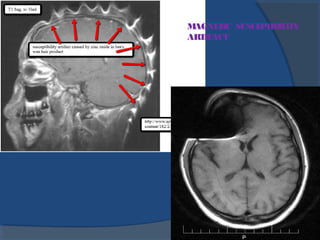

4.Magnetic susceptibility and metal artifacts:

•At theinterfacebetween two tissueswith different

magnetic susceptibilities, therearelocal distortions

in themagnetic field responsiblefor asignal loss

(and sometimesan imagedistortion).

•Theseartifactsaremuch stronger in presenceof

metal.

Remedies:

•Useof Spin echo sequences

•Removing all metallic objests

MAGNETIC SUSCEPTIBILITY

ARTIFACT